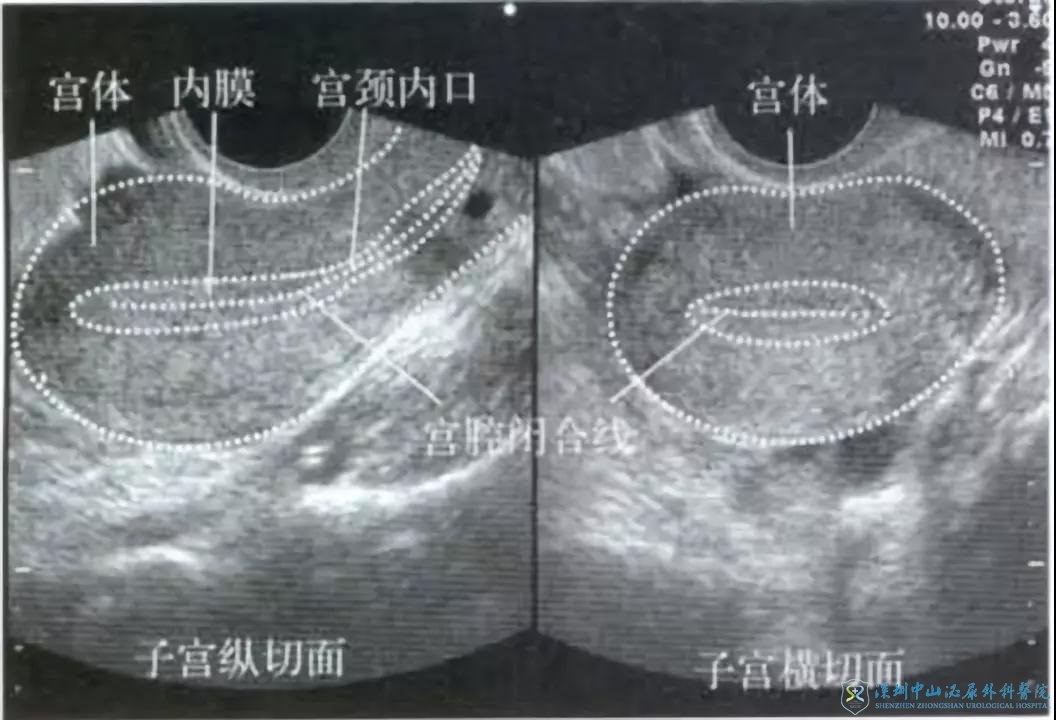

对于行辅助生育治疗的女性,B超基本都是贯穿于整个治疗过程中的。在不同的阶段,医生的检查会有所侧重,但通常我们主要是监测卵泡及内膜的生长发育情况,以及排除一些病理情况,如卵巢囊肿或输卵管积水等。例如在第一次B超时医生主要进行卵巢功能的评估,也就是小卵泡的计数,同时也会注意观察内膜的厚度及形态等。通常子宫内膜在不同的发育阶段会有所不同,如有需要,我们会在进入周期前进行内膜的监测。在月经期,内膜通常是薄的,而随着卵泡的发育,子宫内膜会逐渐增厚,排卵前内膜厚度8mm以上,且内膜形态为A型(也就是通常所说的“三线征”)则认为是较为理想的状态。排卵后,由于孕酮的升高,内膜变为B型,并逐渐向C型转化。